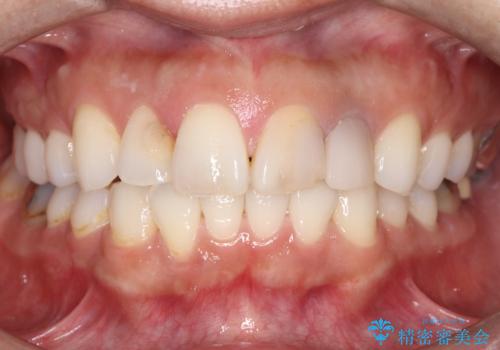

緻密な色合わせと形態調整を重ねた結果、長年のコンプレックスであった前歯の欠けや変色が解消。機能性と審美性が完璧に調和した、自信を持って笑える美しい口元を実現することができました。